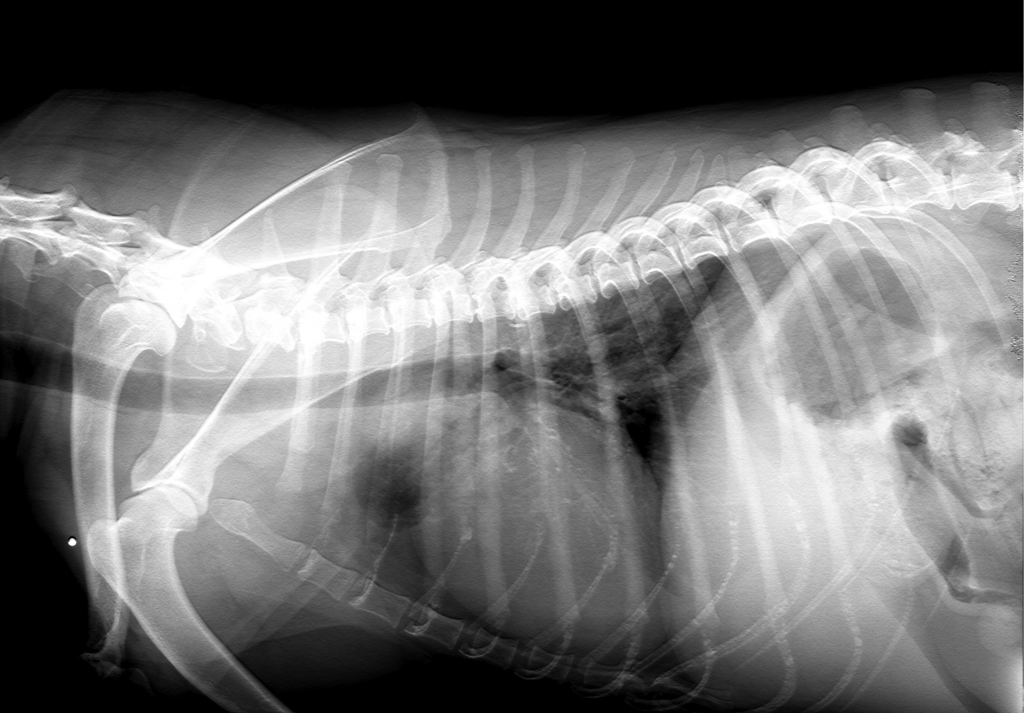

Chest X-ray:

Visualization of the trachea, lungs, heart, etc.